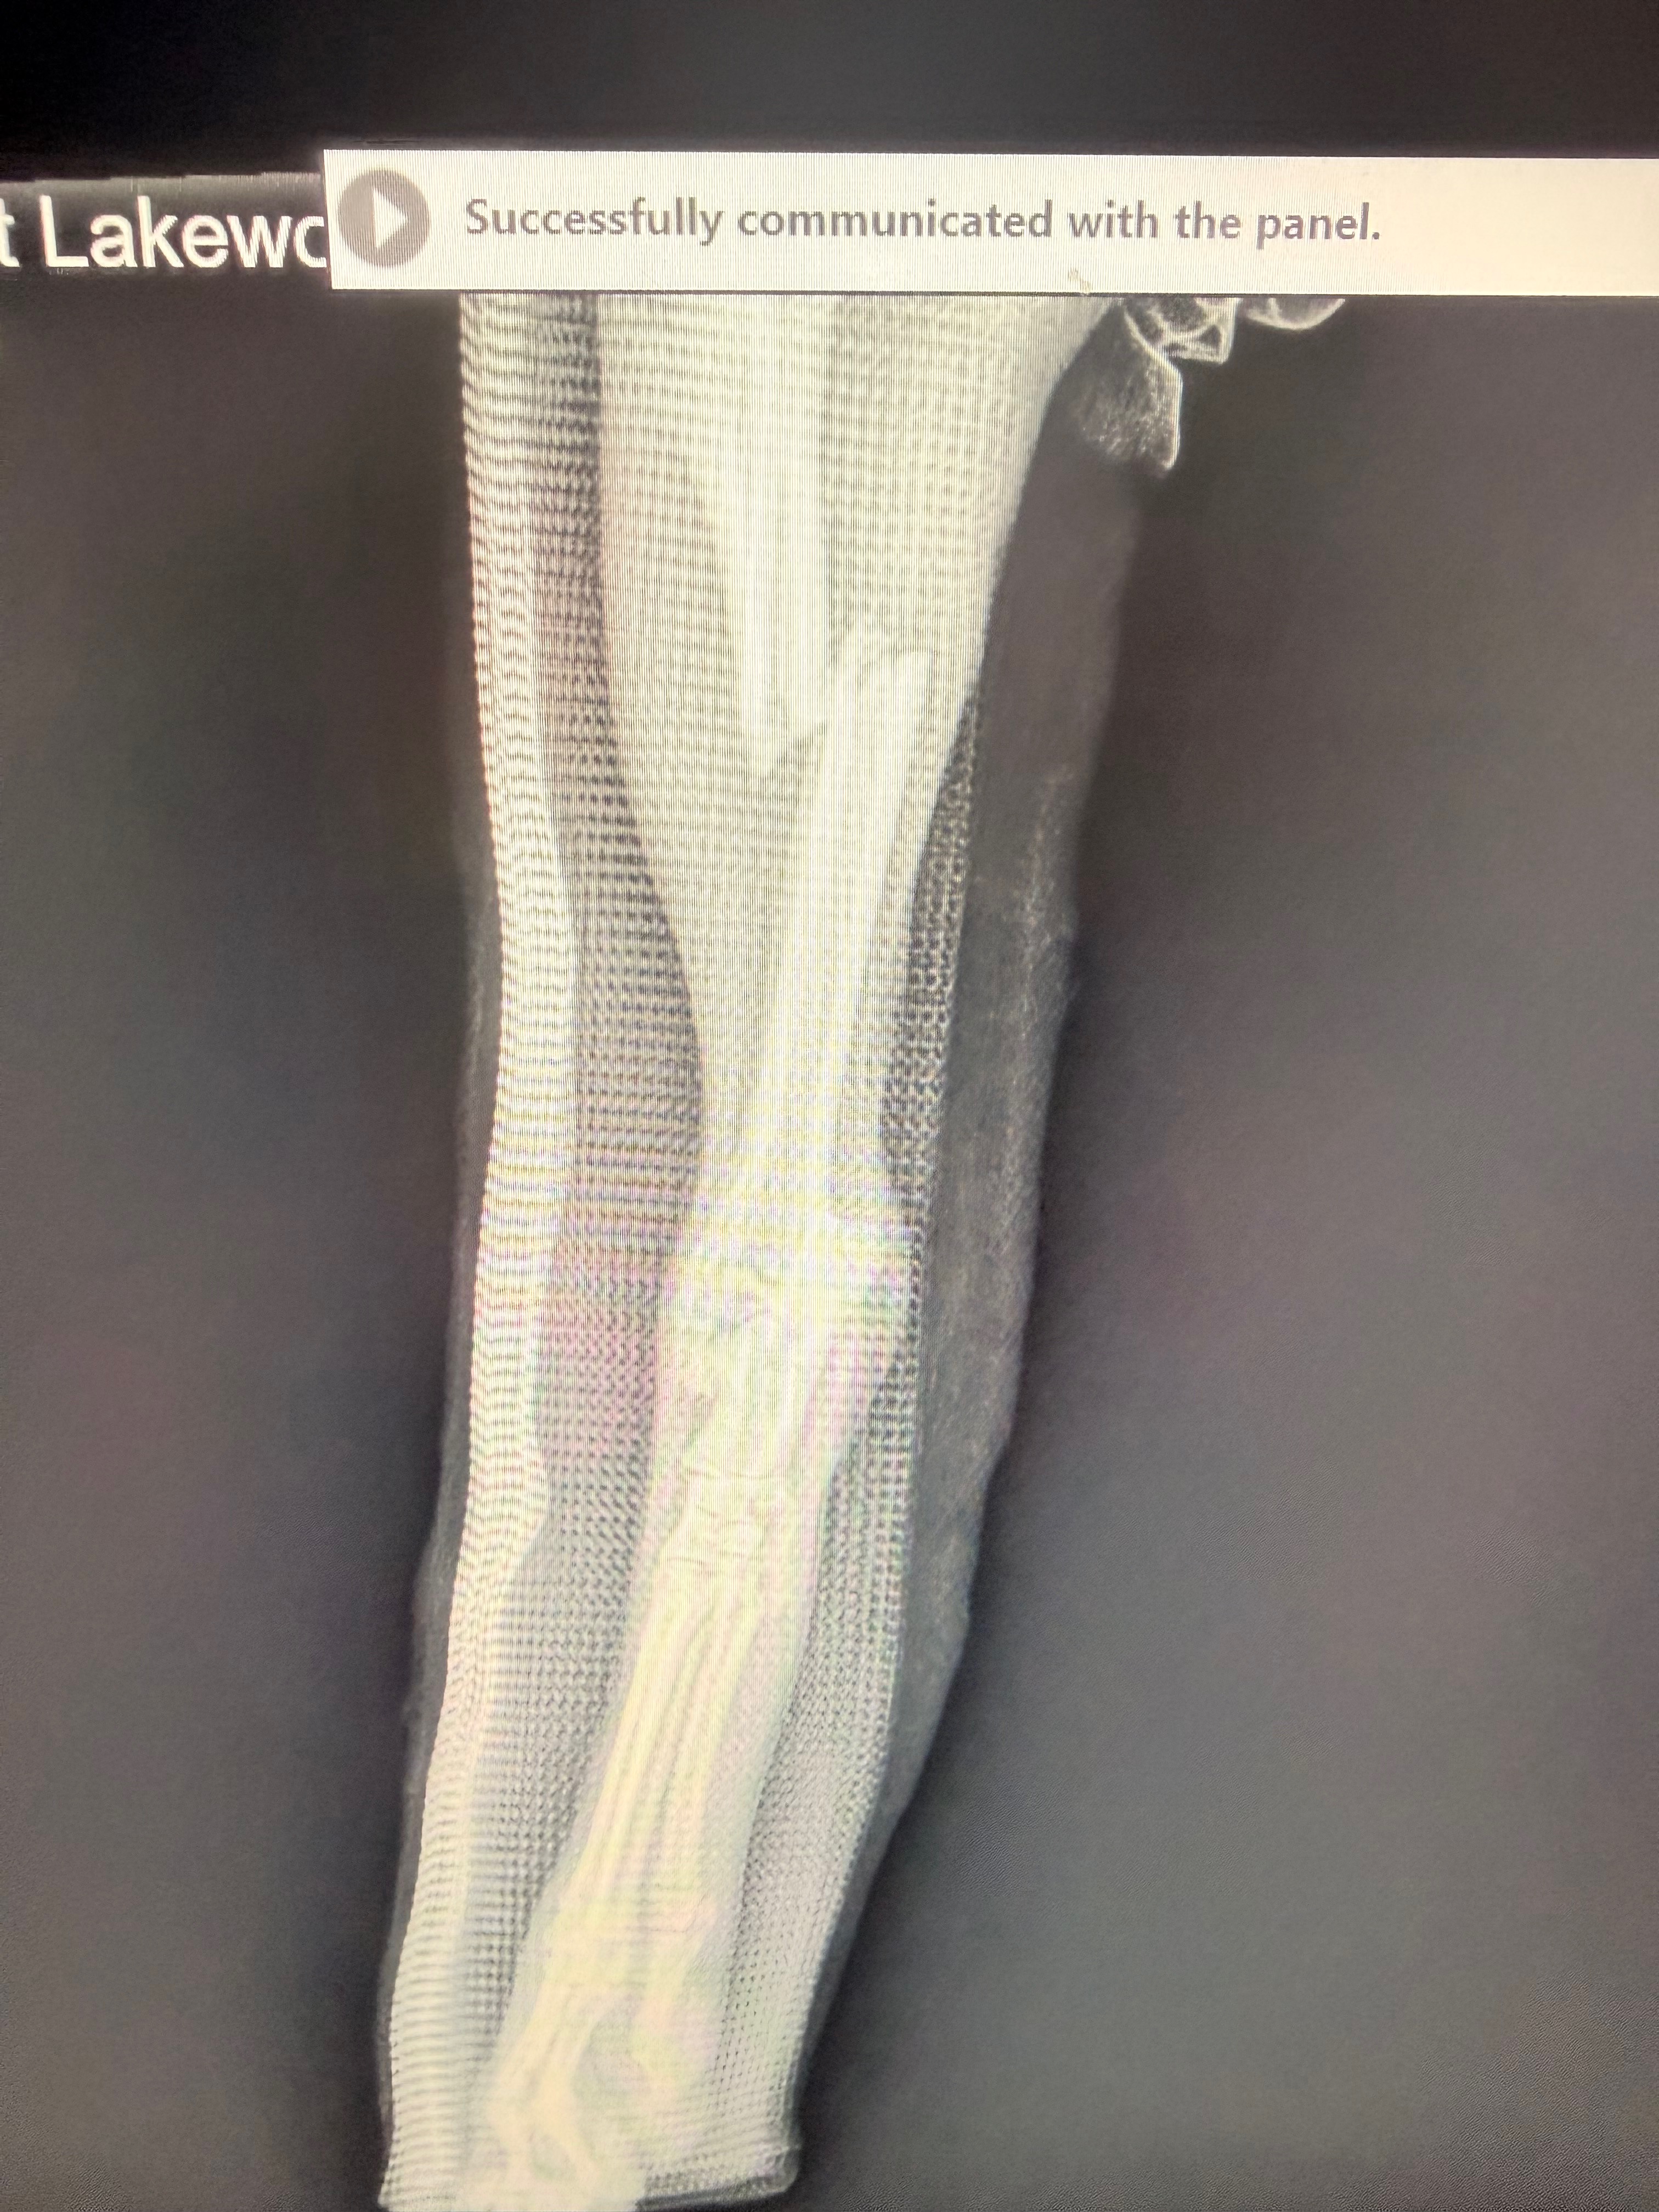

Rescued from Miami-Dade Animal Services, this sweet baby girl came to us with what was thought to be a healing broken leg. Unfortunately, their X-ray machine was down, so everyone hoped the cast she arrived in was doing its job.

But once we brought Shayla to VMC at Lakewood Ranch, the truth came out…

Her leg is completely broken.

And not just one break — she’s facing a major, painful injury.

The surgeon laid out three options:

1️⃣ Amputation

2️⃣ Bone manipulation + recast

3️⃣ Full surgical repair with plates + screws

And as soon as we heard the words: “She’s young, she deserves a real chance at a full life. Surgery will heal faster, reduce infection risk, shorten casting time, and give her the best chance at running again.”